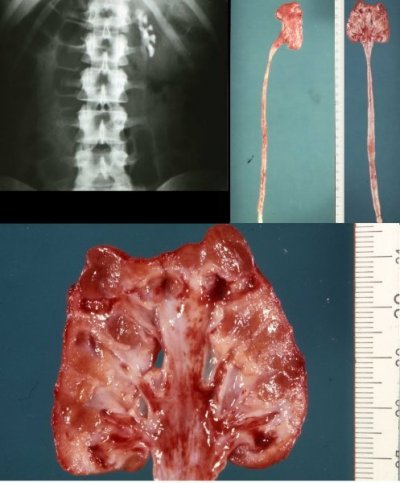

Bei der jungen Erwachsenen fand sich eine nahezu stumme Niere rechts bei Nierenarterienstenose links. Bei dem schwer einstellbaren Hypertonus wurde nach Stentimplantation in die rechte Nierenarterie die linksseitige Nephrektomie der kleinen Niere durchgeführt. Das Organ zeigte eine weitgehend glatte Oberfläche und auf der Schnittfläche einen schmalen Parenchymsaum sowie deutlich vermehrtes Hilusfettgewebe (Abbildung 24).

Histologisch ergab sich eine stenosierende Intimafibrose der intrarenalen Nierengefäße. Die Glomerula, z.T. sklerosiert. Die Tubuli größtenteils atrophiert. Das Interstitium war geringradig entzündlich infiltriert. Ob hier eine vaskuläre Ursache und oder pyelonephritische Prozesse zur kleinen Niere geführt haben, bleibt letztlich unklar.